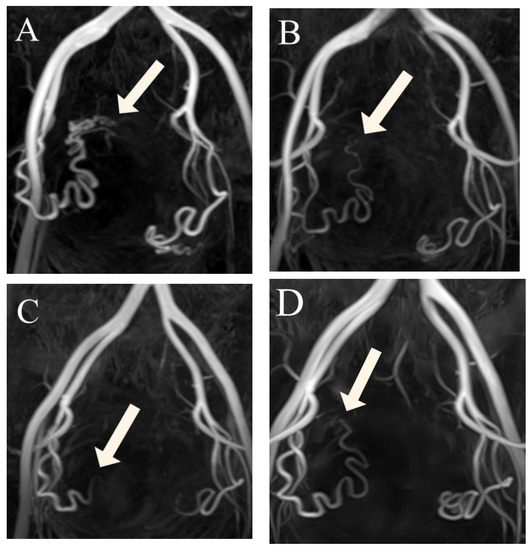

Figure 4.

(A–D) Three-dimensional non-contrast-enhanced magnetic resonance angiography image from a 48-year-old woman, suggesting that luminal recanalization of the uterine arteries did not occur after uterine artery embolization. (A) Before uterine artery embolization: visualization of the right UA (arrow) forming the peritumoral plexus (score 4). (B) Three months after uterine artery embolization: visualization of the right uterine artery (arrow) until the ascending segment (score 3). (C) Six months after uterine artery embolization: visualization of right uterine artery (arrow) until the transverse segment (score 2). (D) Twelve months after uterine artery embolization: visualization of the right uterine artery (arrow) until the transverse segment (score 2).